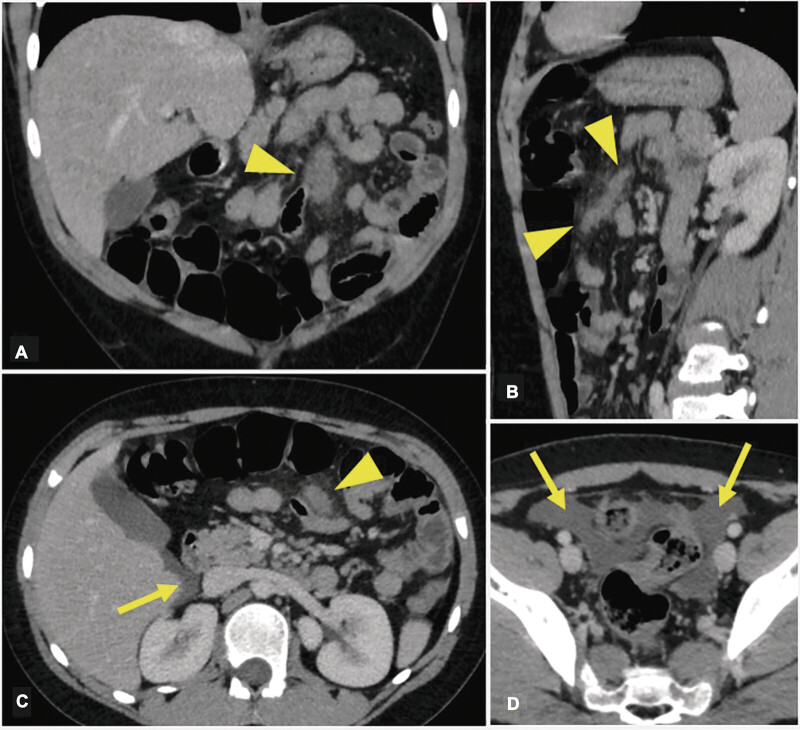

肠系膜剪切,由于肠系膜突然拉伸造成的损伤,是一种罕见的疾病,研究仍然很少,特别是在儿科人群中。通常由创伤引起,其表现可以从非特异性和模糊的腹部症状到需要紧急手术干预的急性腹部和腹膜炎。统一的管理策略尚未到位。我们描述的情况下,一个10岁的男孩谁提出了弥漫性腹痛持续1天,2天后,他持续钝性腹部外伤与肘部在足球比赛。他的血流动力学和临床稳定。计算机断层扫描显示肠系膜根部左上象限软组织增厚,周围有轻度炎症性肠系膜脂肪搁浅,提示肠系膜剪切。由于生命体征稳定,体检腹部柔软,血红蛋白无下降,故决定保守治疗。患者入院观察,经过频繁的腹部检查,稳定的实验室结果和腹部影像学检查,患者出院回家,没有任何手术干预。对于病情稳定的患者,保守治疗可能是成功的,但没有令人担忧的物理、实验室或影像学发现。观察和密切监测对于发现需要手术干预的复杂病例仍然至关重要。

Mesenteric shear, injury due to sudden stretch of the mesentery, is a rare condition that remains poorly studied, especially in the pediatric population. Often resulting from trauma, its presentation can vary from nonspecific and vague abdominal symptoms to an acute abdomen and peritonitis requiring urgent surgical intervention. Unified management strategies are not yet in place. We describe the case of a 10-year-old boy who presented to the emergency department with diffuse abdominal pain of 1 day duration, 2 days after he sustained blunt abdominal trauma with an elbow during a soccer match. He was hemodynamically and clinically stable. Computed tomography scan revealed soft tissue thickening in the left upper quadrant at the root of the mesentery with mild surrounding inflammatory mesenteric fat stranding, suggesting mesenteric shearing. With stable vitals, a soft abdomen on physical exam, and no drop in hemoglobin, the decision was made to treat the patient conservatively. The patient was admitted for observation, and after frequent abdominal exams, stable laboratory results, and abdominal imaging, he was discharged home without any surgical intervention. Conservative management can be successful in the case of a stable patient without alarming physical, laboratory, or imaging findings. Observation and close monitoring remain essential to detect complicated cases that require surgical intervention.